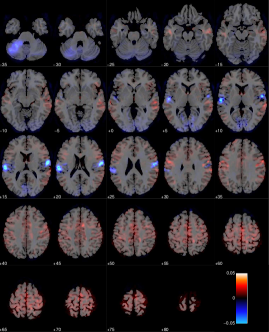

We construct a -nearest neighbor graph using the nonlinear affinity . Figure 14 shows the 4 leading non-trivial global eigenvectors projected onto a sliced brain. Note that the first slice (top left) in such an image corresponds to the bottom of the brain, whereas the last slice (bottom right) corresponds to the top of the brain. The non-trivial global eigenvectors aim to span the most dominant sources of variation in the data, which in this particular dataset appears to stem mainly from the primary visual cortex (V1), and a frontal/posterior contrast apparent in the second global eigenvector. Importantly, the global eigenvectors are typically not associated with the interesting features of the task but rather general signal variation, which may be due to visual presentation of the stimuli (visual cortex) and often physiological noise sources typically dominant in the lower slices of the brain near large arteries.

Using a probabilistic functional atlas created by averaging across multiple subjects [17], we carry out two experiments based on semi-supervised eigenvectors. Specifically, we construct semi-supervised eigenvectors seeded in Primary Motor Cortex (PMC), known to be highly involved in the subject task [21], as well as semi-supervised eigenvectors seeded in Primary Auditory Cortex (PAC), that is not expected to carry much signal with respect to our target variable [39]. The seed regions are highlighted in Figure 15(a) and 15(b).

Figure 16 and 17 shows respectively the leading 4 semi-supervised eigenvectors, each having a correlation of with the seed, and respectively seeded in PMC and PAC. As expected the semi-supervised eigenvectors are dominant near the seed region but are able to spread to related regions which carry information about important signal variation. For the PAC seed the first eigenvector appears to capture the general pattern of signal variation in part of the cortex that focus on auditory processing. The remaining three eigenvectors appear to span specific signal variations in the PAC that are more specific to subregions with the auditory cortex.

Likewise the first semi-supervised eigenvector from the seed in the PMC reveals other dominant parts of the motor network including the remaining parts of the PMC (posterior part of Brodmann area 4), somatosensory cortex (Brodmann areas 1,2 and 3) and the premotor cortex (Brodmann area 5). The remaining semi-supervised eigenvectors again focus on more localized sources of signal within these areas as well as signal variation in the primary visual cortex (Brodmann area 17), which is to be expected as the visual presentation of stimuli is related to motor function in the present task.

For comparison in our classification task, we consider the leading global eigenvectors of the graph Laplacian, as well as simply extracting the time series as specified by the seed regions. For all of the considered feature extraction approaches we use either the projected or extracted time series as data for a linear SVM that is responsible for the downstream classification task. Figure 15(c) summarizes the classification accuracies obtained by performing leave-one-out cross validation as a function of the number of components. For each semi-supervised eigenvector we fix where is the number of components. Hence, for two components, each correlates with the seed, and so forth. In the same plot, the dashed blue line corresponds to classifying the brain state using only voxel time series in the region as defined by PAC. Unsurprisingly, for the dashed green line, corresponding to PMC, it is evident that the primary motor cortex is a much better proxy for predicting motor responses. Due to inter-subject variability there is no guarantee that the rigid body realignment will align the seed perfectly with the physical region, which explains why the data-driven global eigenvectors are able to yield an even higher accuracy than the PAC time series. Also seen is the “bump” in classification accuracy for the global eigenvectors, when we reach 4-5 components. Thus, for this particular dataset, relevant parts of the are signal are captured in this regime.